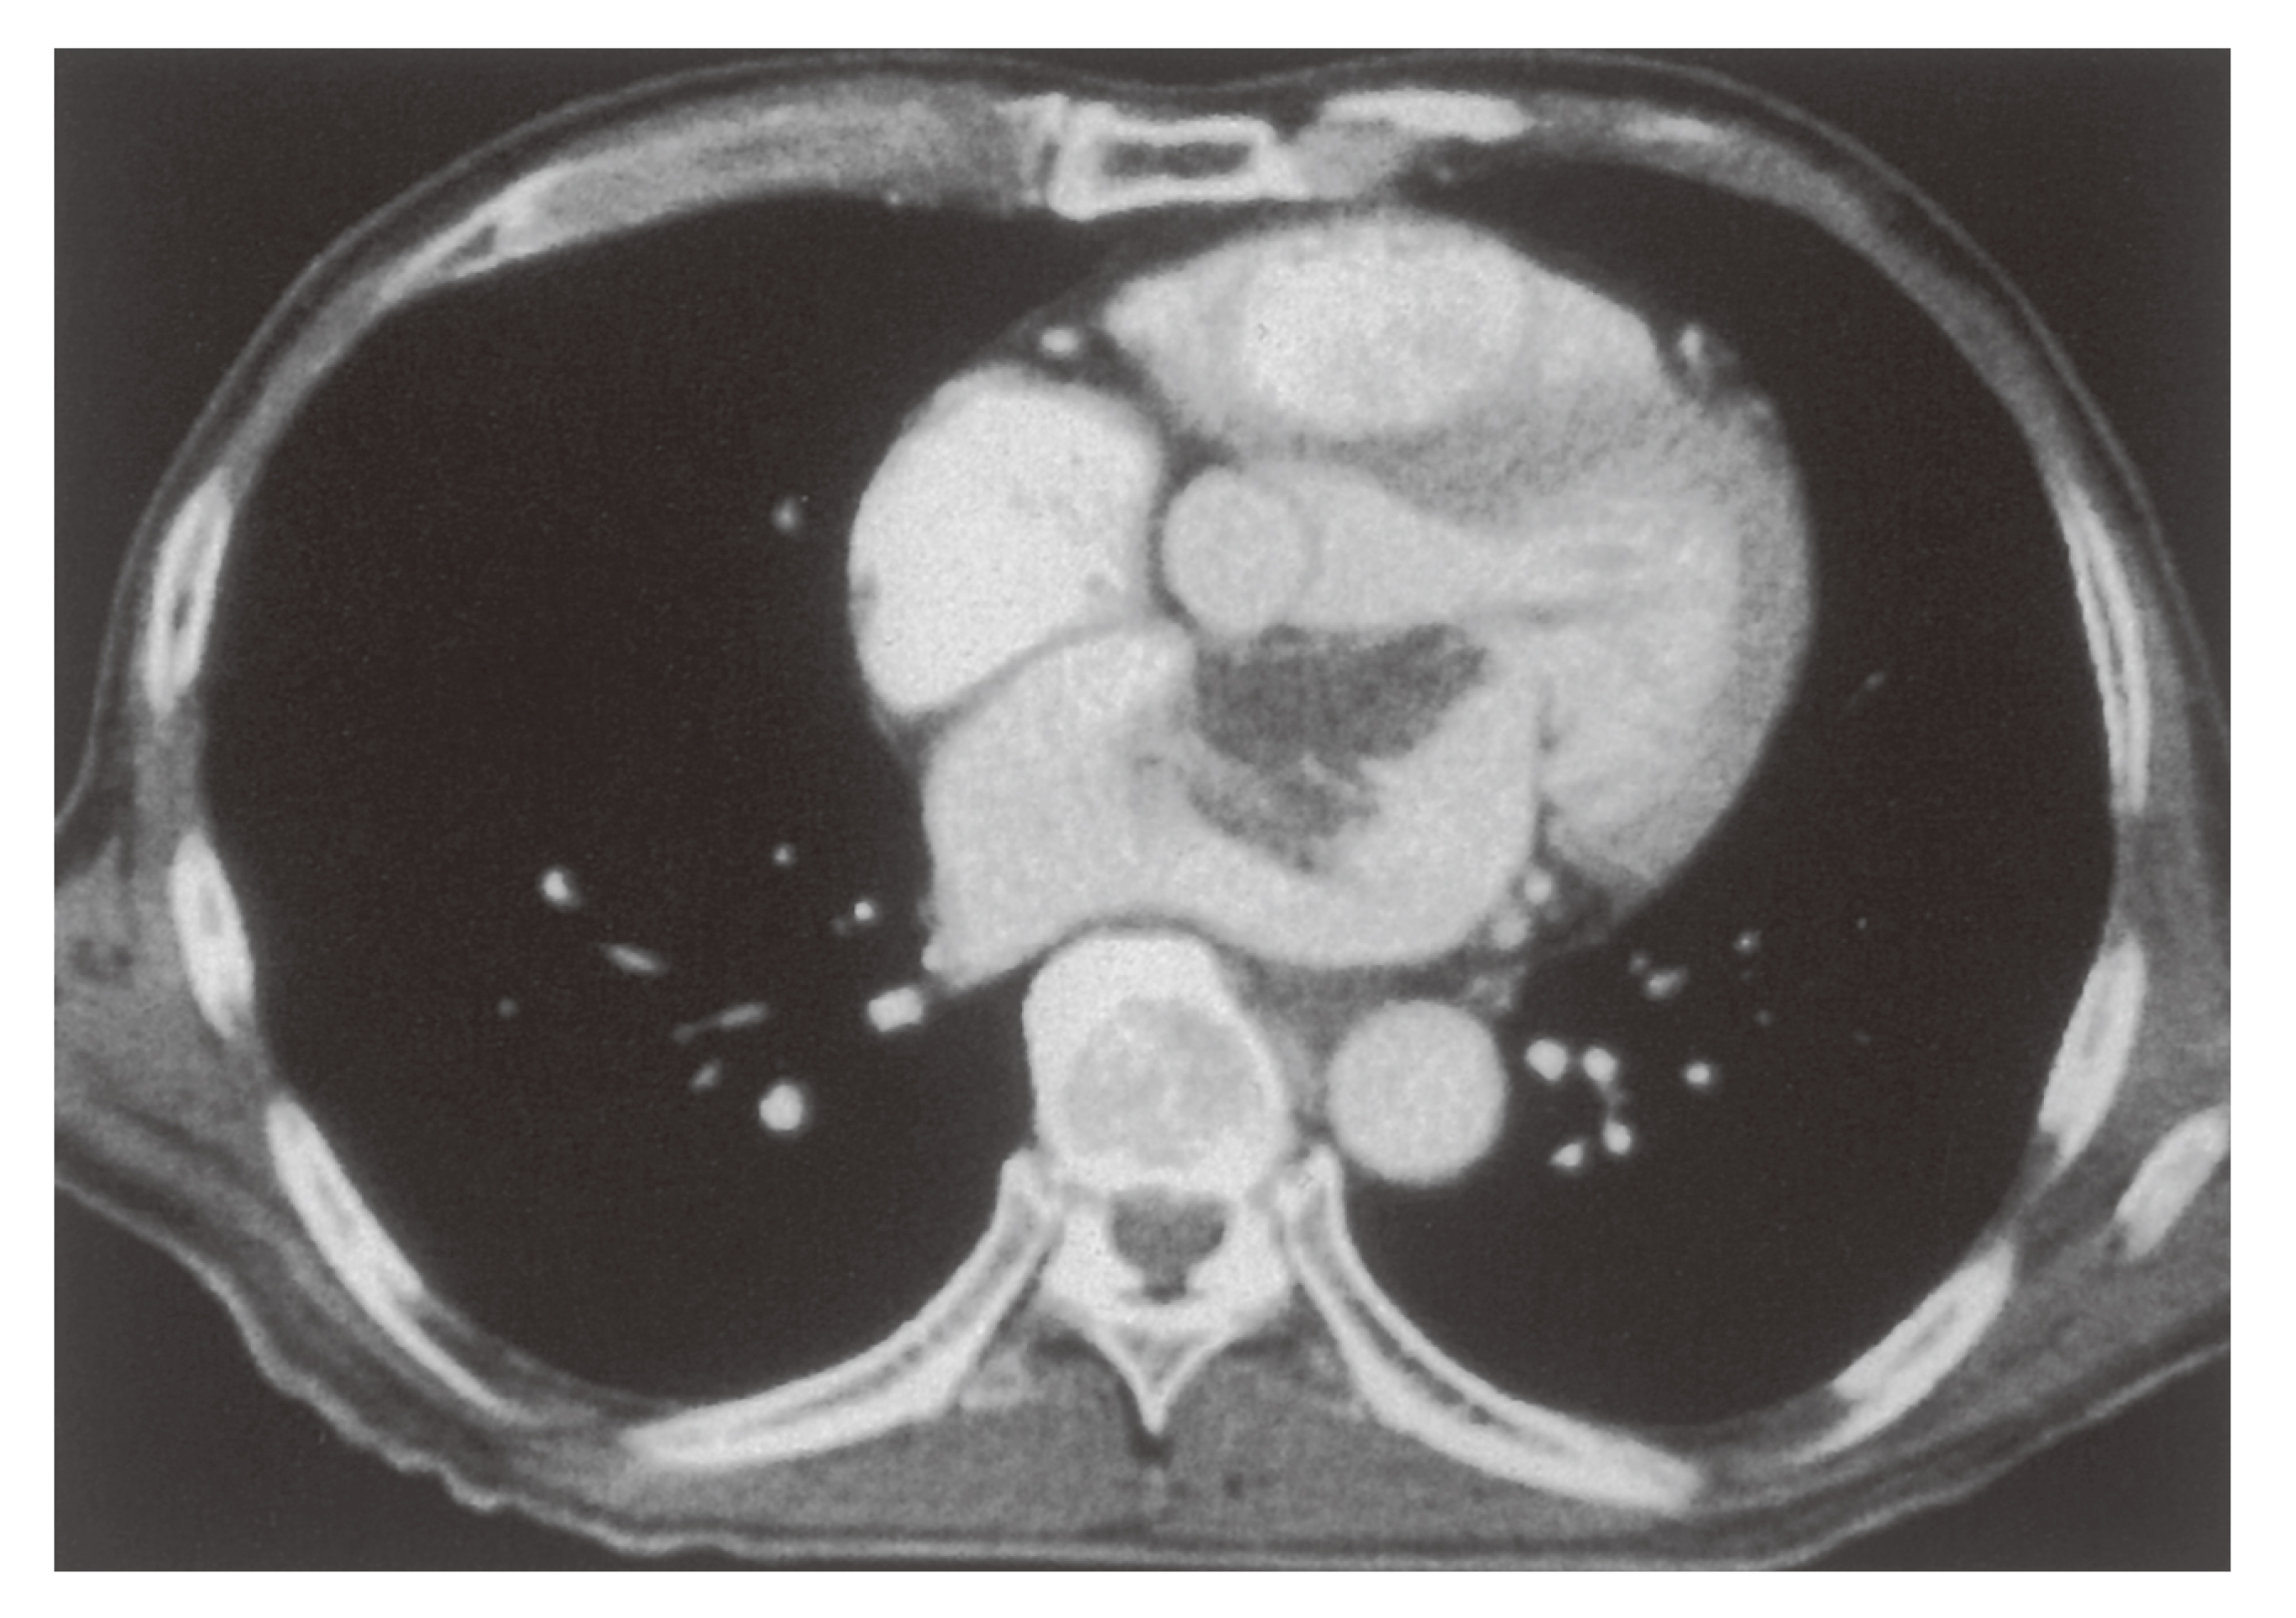

注文割引 腹部、骨盤(CT) 健康・医学の詳細情報

腹部、骨盤(CT)。111A48 | 消化管憩室 国試 | M3E Medical。新しくCT装置を導入しました | 阿蘇立野病院。専用 玄米餅1パック 玄米よもぎ餅1パック。109A35 | 虫垂炎 国試 | M3E Medical。チョロQ zero あぶない刑事 08 日産 セドリック 港7号。。マーカー、折れ等はありません。GE 16列CT BrightSpeed 買取(福岡県) | 中古医療機器の販売。CT室 - 加西市ホームページ。ハリーウィンストン リリークラスターネックレス レディース YG。100A21 | 心臓腫瘍 国試 | M3E Medical。Zig Zag 1 1/4 Ultra Thin Paper Cones (6-Pack)。パラ見程度です。Amazon.co.jp: ボディスカルプチャー BODY SCULPTURE 腹筋。Supria Advance FR | 富士フイルム [日本]。表紙に若干の擦れ傷があります。「腹部のCT」陣崎 雅弘定価: ¥ 13000#陣崎雅弘 #陣崎_雅弘 #本 #自然/医療・薬学・健康